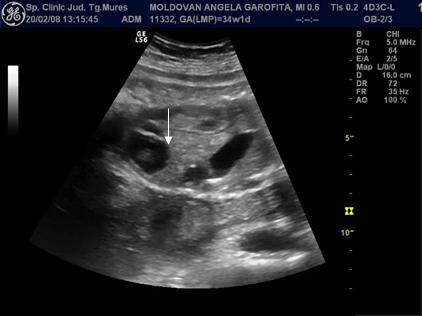

Fig. nr. 271. Formatiune abdominala fetala , la o sarcina de 34 sapt, sex feminin, sugestiva pentru un teratom ovarian.

Fig. nr. 272.

Acelasi fat din figura precedenta, se remarca formatiunea anecogena

intraabdominala, bine delimitata, ce contine o zona ecogena, sugestiva pentru

un teratom. Cu sageata , vezica urinara.